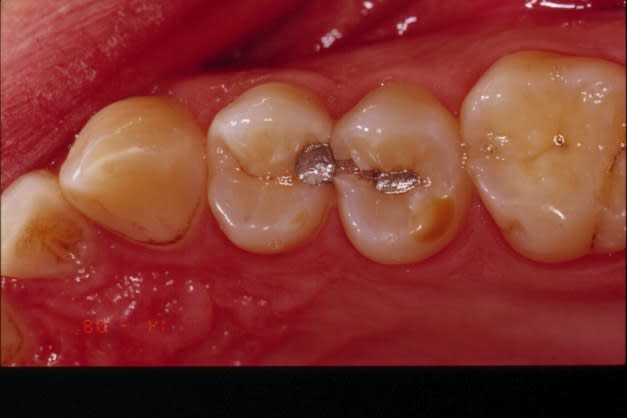

Sur une cavité profonde, un composite vaut un nécro. Combien trouve-t-on de 4èmes consécutifs !

donnot, un composite direct n'est pas indiqué pour les grosses cavités profondes, et quand il l'est , il doit être fait dans les règles de l'art. càd, digue, protocole rigoureux , etc. si c'est trop gros, c'est inlay. je n'ai plus de machine à Ag depuis qu'ils ont interdit le vrac: si tu crois que je fabrique des nécros à longueur de journée, tu te trompes. avant de critiquer un matériau, commence par bien cerner son indication.

donnot, il m'est arrivé de réaliser carrément des coiffages au composite, d'autres personnes ici en ont déja parlé, collage d'inlay sur pulpe exposée, au variolink: je te garantie qu'un test de vitalité est réalisé tout les six mois sans souci depuis des années.

Je ne voulais, en effet, que parler d'expérience clinique, donc de toxicité pulpaire. On voit des amalgames très anciens, très proches de la pulpe et quasiment pas de mortifications.

Par contre, avec des composites, il est fréquent de trouver des gangènes, surtout sur les incisives sur lesquelles il n'y a pas vraiment d'autre possibilité.

J'ai aussi essayé des coiffages et j'ai été étonné de constater que la vitalité pulpaire est mieux assurée sur une pulpe exposée que sur une pulpe trop proche mais non ouverte. Pourquoi ? Je ne sais pas. Mais je n'utiliserais jamais une telle dent en support de conjointe.

Quand c'est possible, je préfère sans problème un inlay scellé au verre ionomère ou au polyphosphate.